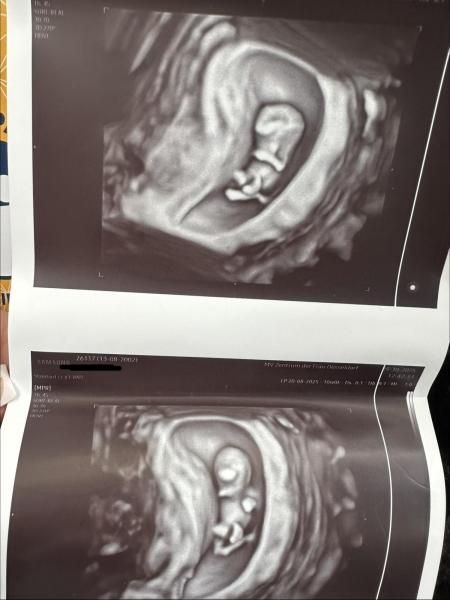

Hallo meine Lieben, ich müsste bei 10+0 sein. Gestern beim Termin habe ich diese schöne US Bilder bekommen. Die aktuelle SSL beträgt 2,84 cm, das kommt mir ein bisschen klein vor... Der Arzt sagt es sieht alles gut entwickelt aus, so wie es sein soll. Das kleine hat auch ordentlich gezappelt so war es schwierig alles auf das US Bild zu bekommen... Mir fehlen da bisschien die menschlichen Züge ... einbisschien kann man ja schon erkennen...  Sahen eure Ultraschallbilder ähnlich aus? Wie war eure SSL bei 10+0? Vielen dank eure Mamiibambii❤️